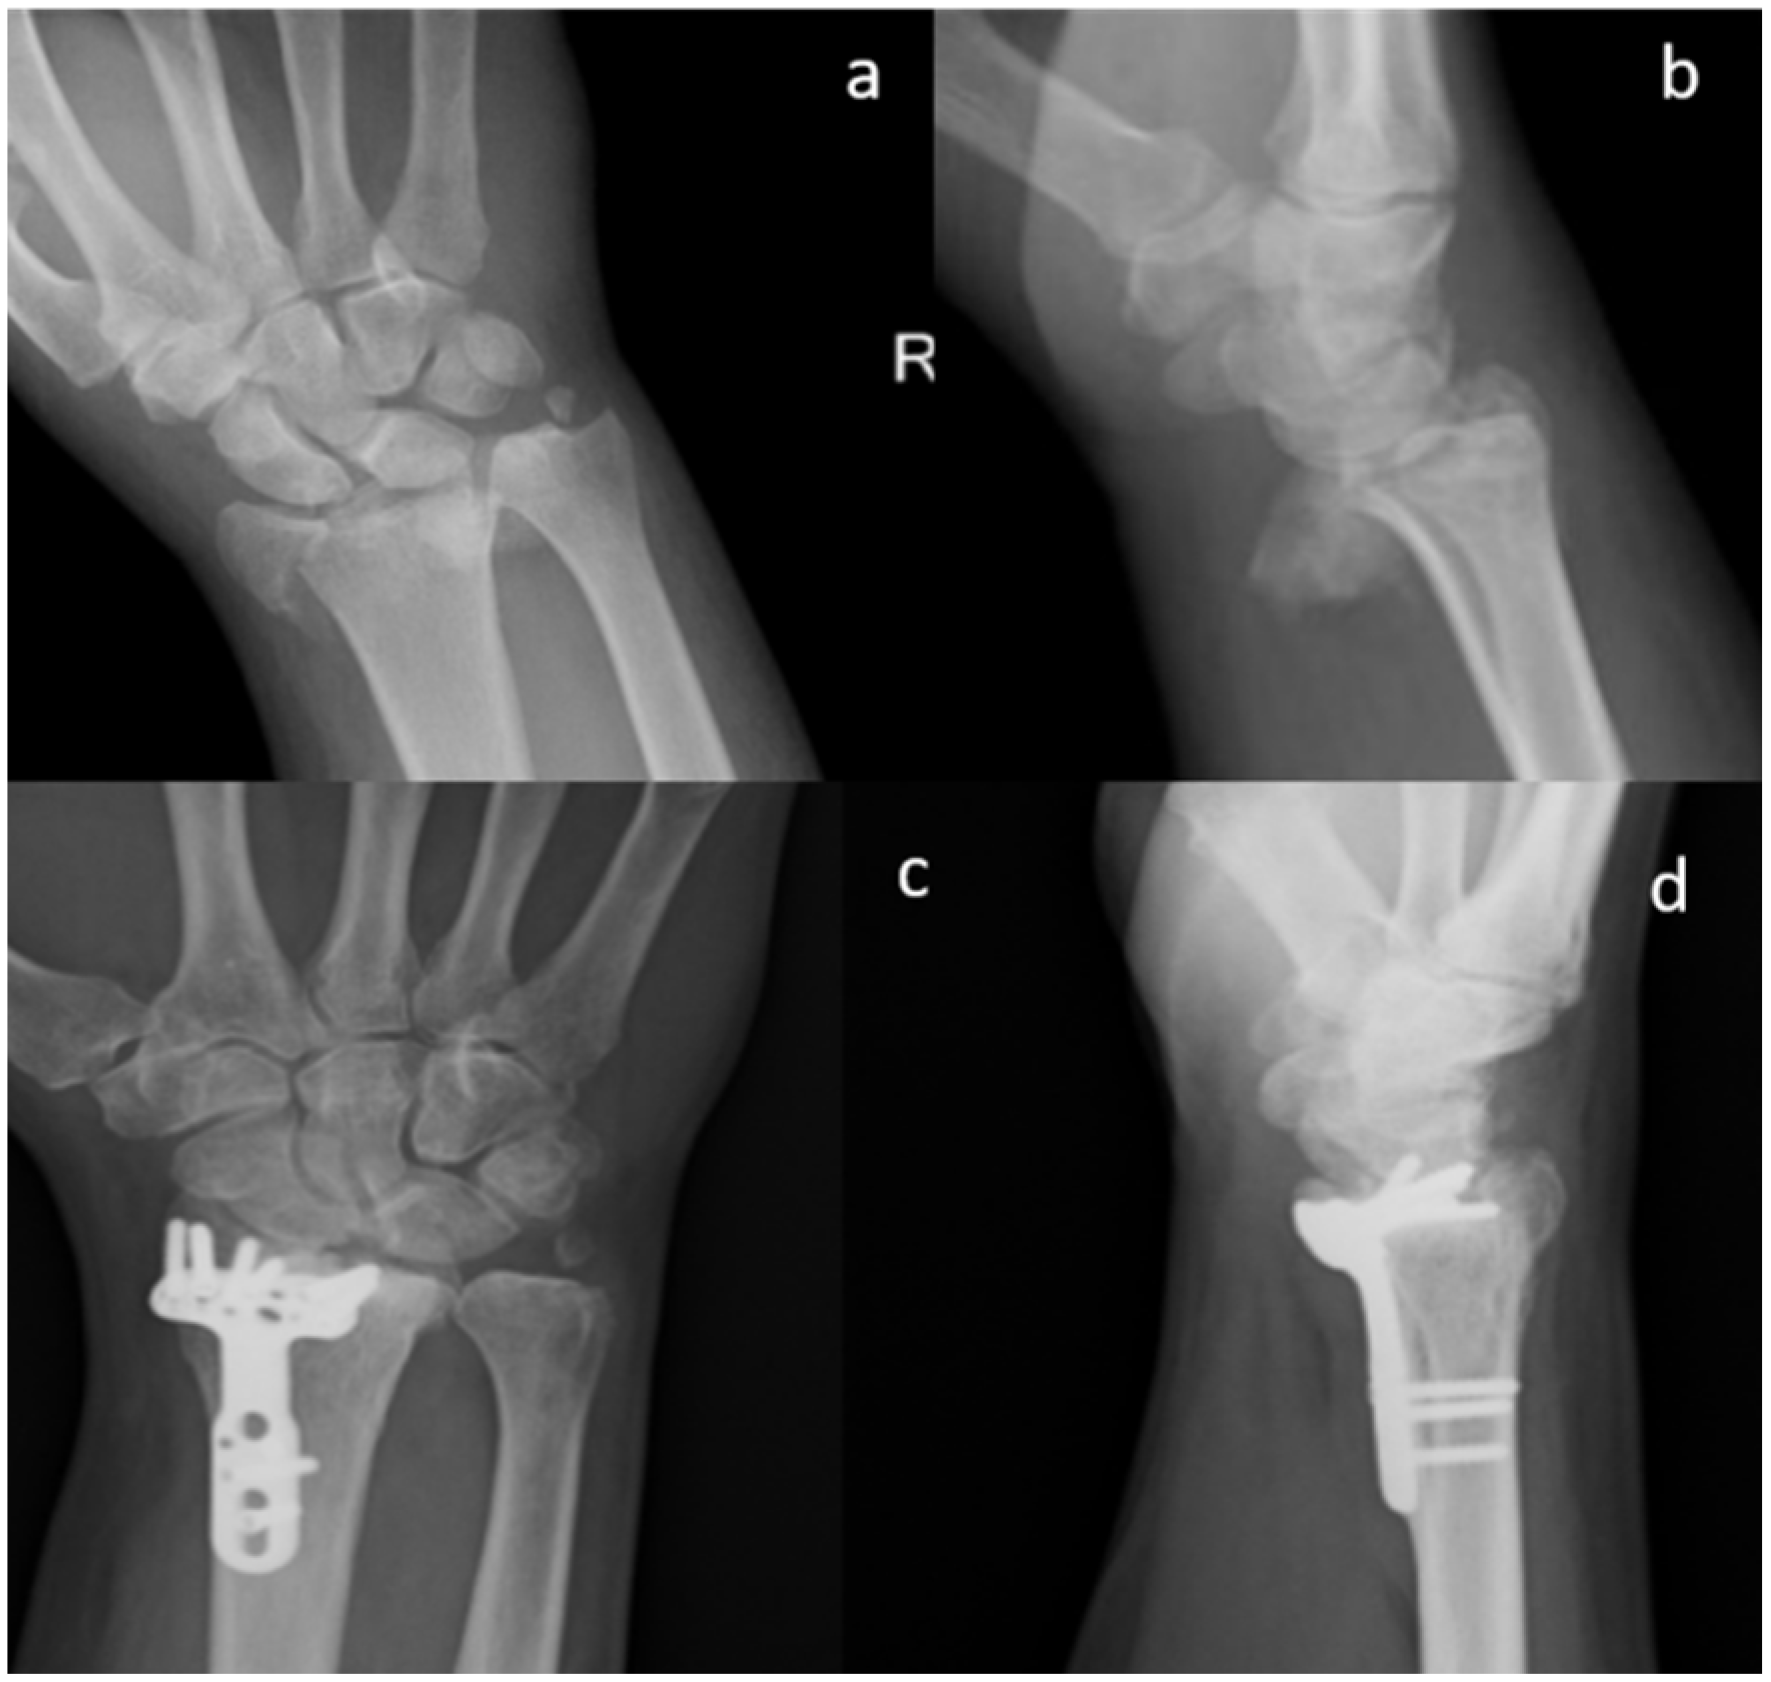

Figure 2.

Standard X-ray of a displaced articular fracture of the distal radius associated with styloid ulna fracture. Preoperative images in AP (a) and Lateral (b) view are compared to post-operative X Ray at 2 months (c,d). The exuberant callus formation can be visualized (Male, 55 yy).

All the patients performed radiographic examinations during regular follow-up. Radiographs were examined for callus formation, bone resorption, implant stability, and SB integration [28] (Figure 1, Figure 2 and Figure 3).

X-ray images of 7 out of 19 patients showed that fractures were consolidated at two months: the radiographic controls, indeed, showed abundant callus formation. An exemplificative case is presented in Figure 2. The remaining 12 patients showed reduced callus formation after two months and performed an additional X-ray imaging check at five months after surgery (exemplificative case shown in Figure 3). In all cases, radiolucency of the xenografts was assessed, which became progressively more similar to that of the surrounding healthy bone tissue.